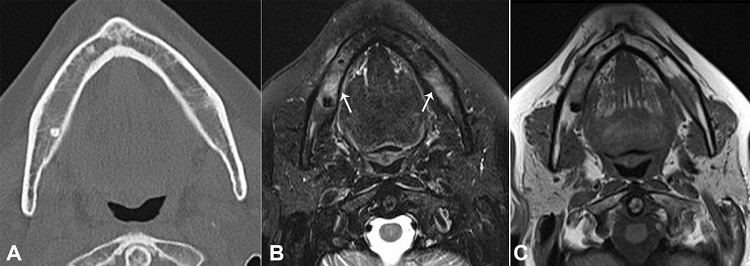

As a result of the patient’s complaint, we identified a small area adjacent to the region of the right mental nerve that was uncomfortable on palpation. No other changes were found by means of cone-beam computed tomography (Figure 2A) and clinical examination. Magnetic resonance features made possible to identify a change in the mandibular body extending to the entire right side (Figures 22C, 33B), coinciding with the clinical complaint, indicating a probable mandibular medullary invasion.